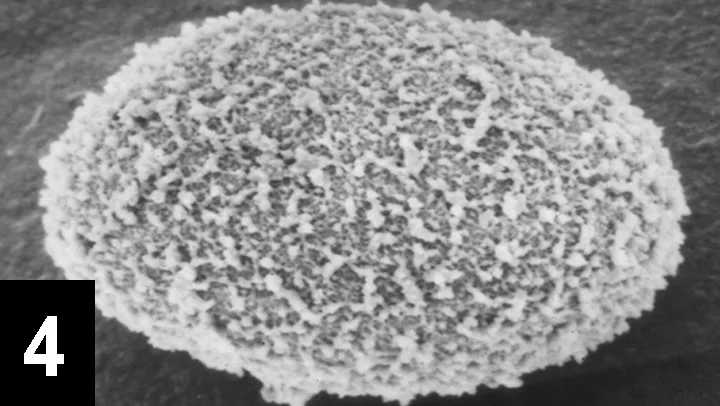

B. procyonis egg under a scanning electron microscope, showing the irregular granular surface of congealed proteins (1260x original magnification)

Figures 4 and 5 show the surface features of B. procyonis and T. canis, respectively, as they would appear with a scanning electron microscope. Another ascarid occasionally seen in dogs, Toxascaris leonina, produces ellipsoidal eggs that are 75 to 85 × 60 to 75 µm and colorless (appear gray, like hookworm eggs), with a smooth surface; they have an embryo that partially fills the egg, and a prominent lipid layer visible inside the shell (Figure 6). An ocular micrometer is essential for accurate measurment.